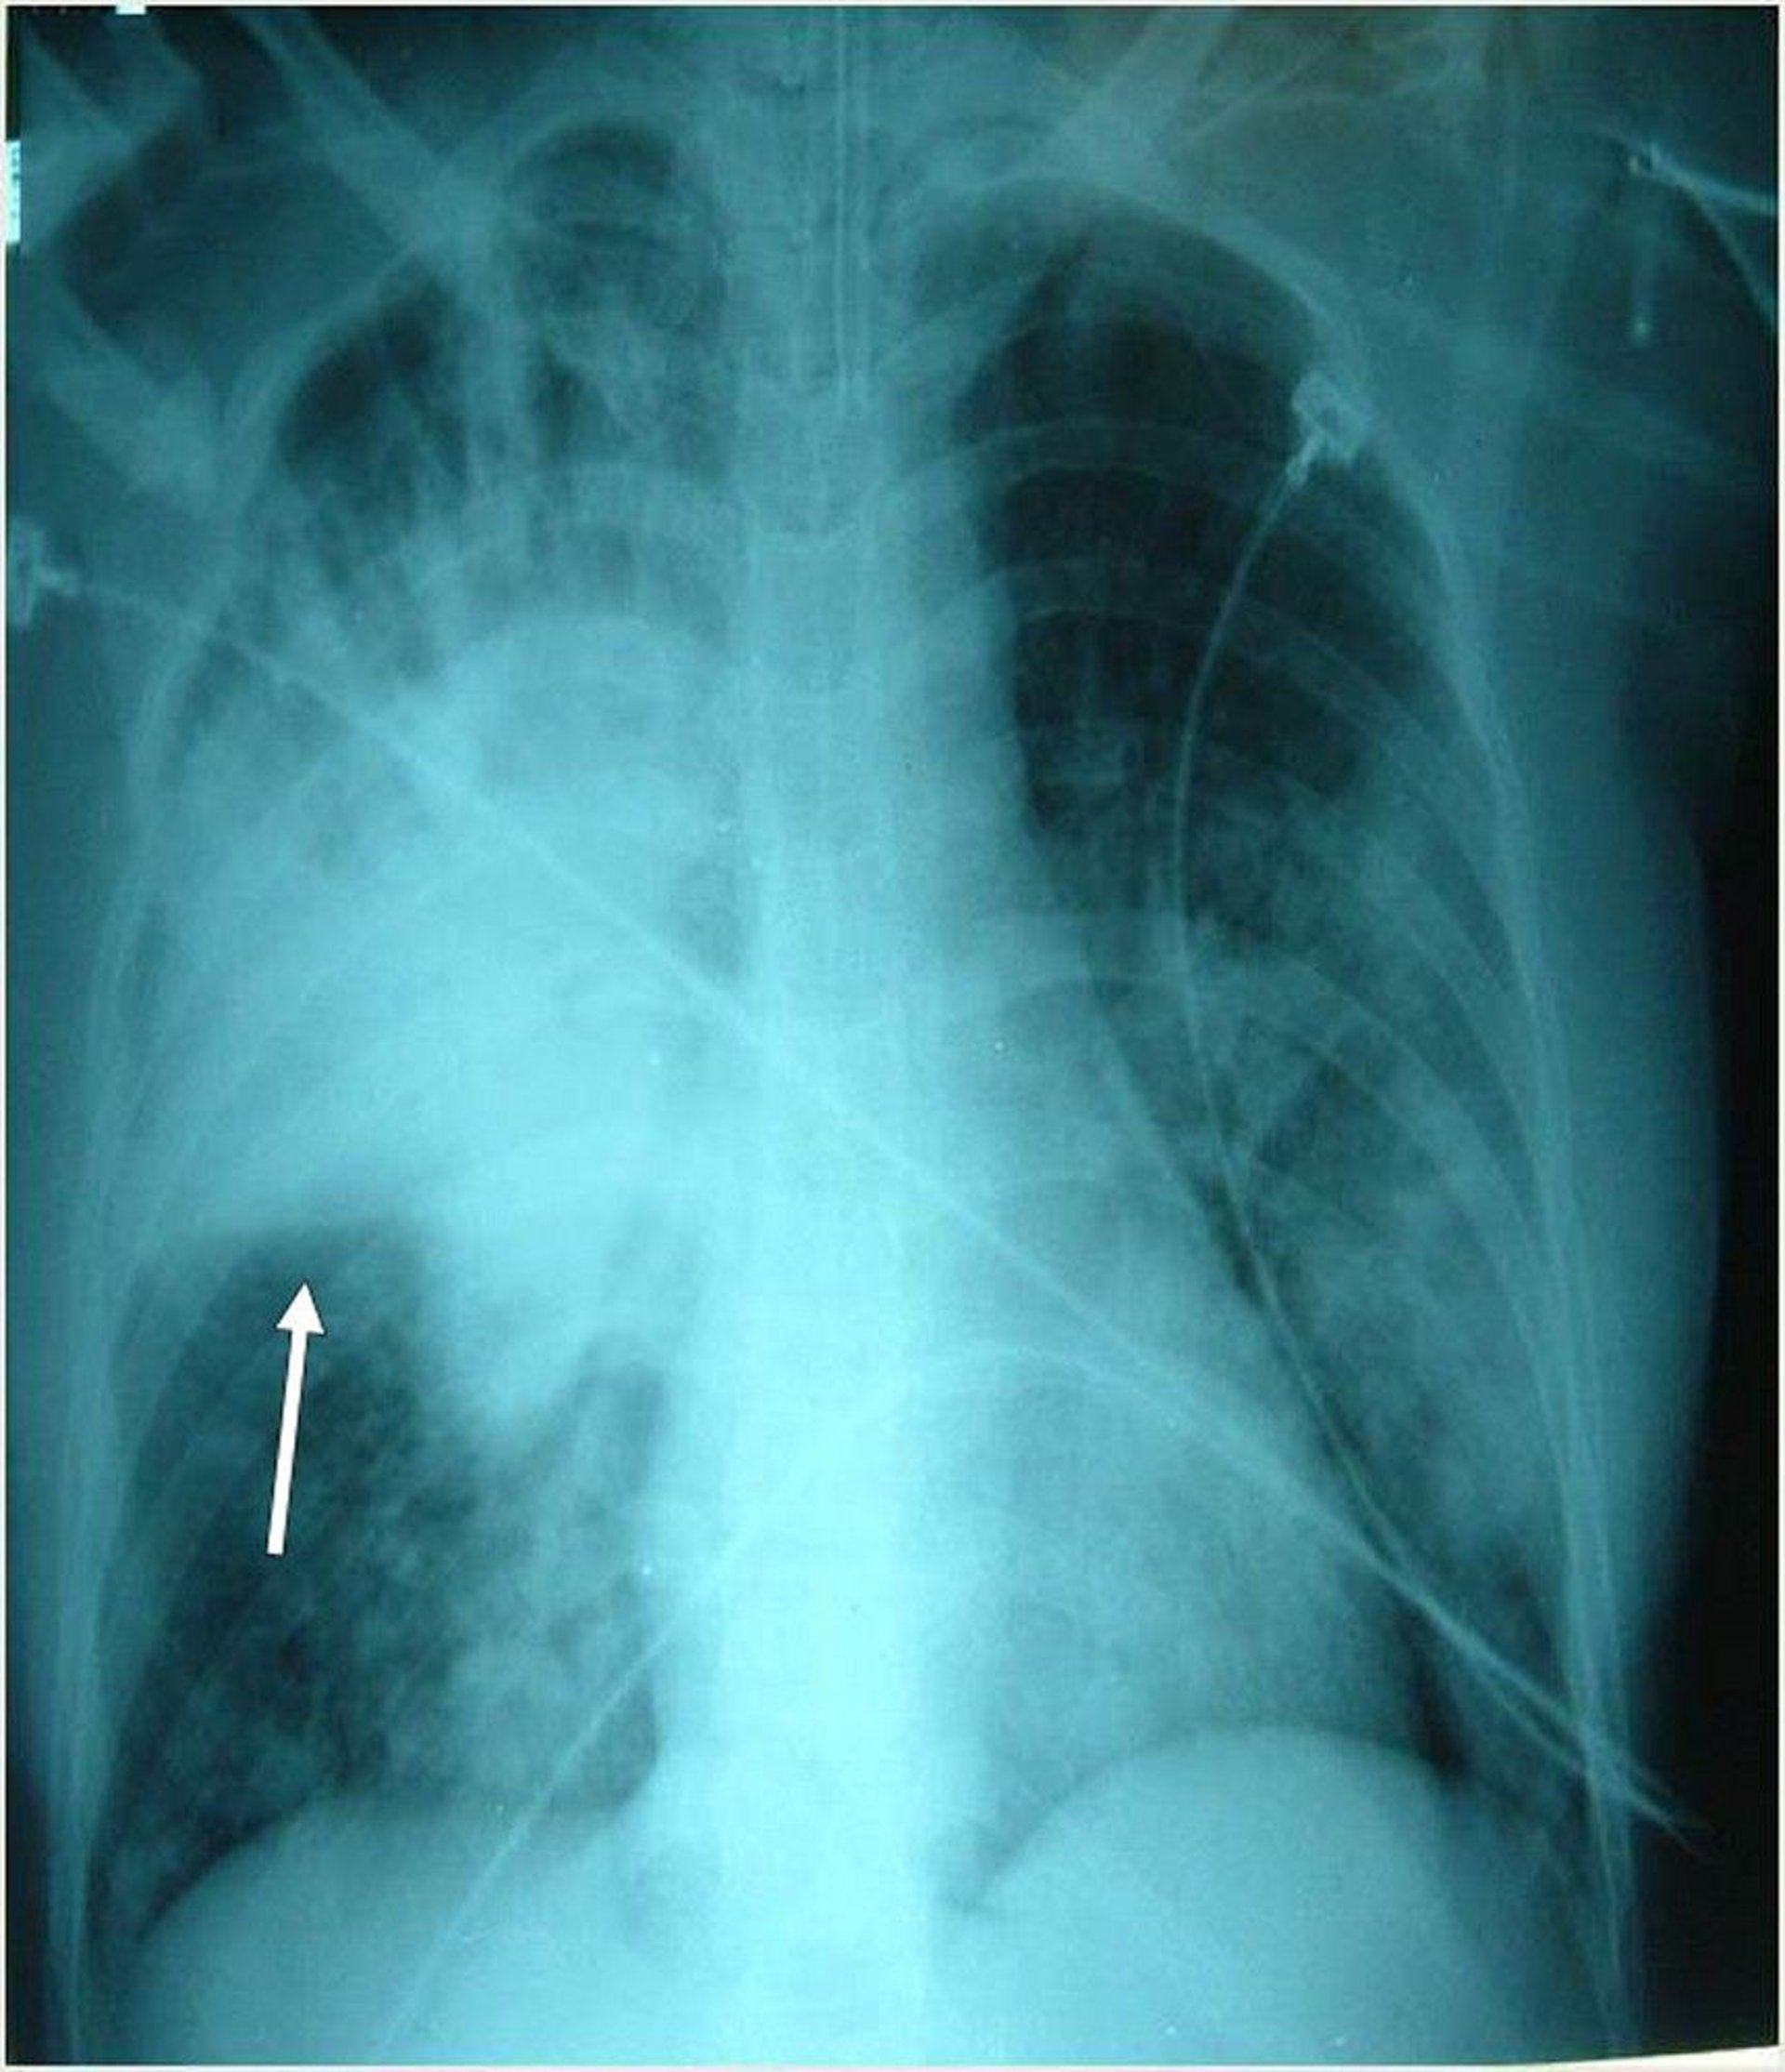

Dieser intubierte Patient weist mehrere bilaterale Infiltrate auf, am prominentesten im rechten Oberlappen. Der Pfeil zeigt die rechte horizontale Fissur an.

Photo courtesy of Thomas M. File, Jr., MD MSc MACP FIDSA FCCP.